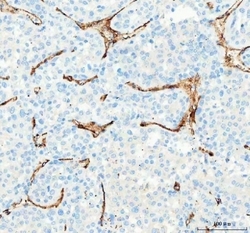

Supportive validation

- Submitted by

- NSJ Bioreagents (provider)

- Main image

- Experimental details

- IHC-P: CD31 antibody testing of human intestinal cancer tissue

- Submitted by

- NSJ Bioreagents (provider)

- Main image

- Experimental details

- IHC-P: CD31 antibody testing of human placenta tissue

- Submitted by

- NSJ Bioreagents (provider)

- Main image

- Experimental details

- IHC-F testing of CD31 antibody and human placenta tissue

- Submitted by

- NSJ Bioreagents (provider)

- Main image

- Experimental details

- IHC staining of FFPE human placental tissue with CD31 antibody. HIER: boil tissue sections in pH8 EDTA for 20 min and allow to cool before testing.

- Submitted by

- NSJ Bioreagents (provider)

- Main image

- Experimental details

- IHC staining of FFPE human liver cancer tissue with CD31 antibody. HIER: boil tissue sections in pH8 EDTA for 20 min and allow to cool before testing.